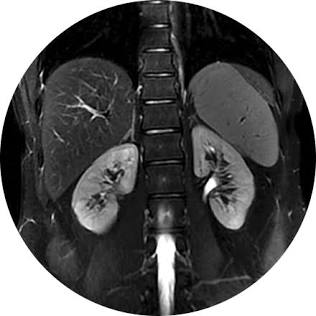

Abdomino-pelvic arterial vascular compression syndromes

A comprehensive review about the abdominal pelvic arterial compression syndrome, typical findings and clinical associations.